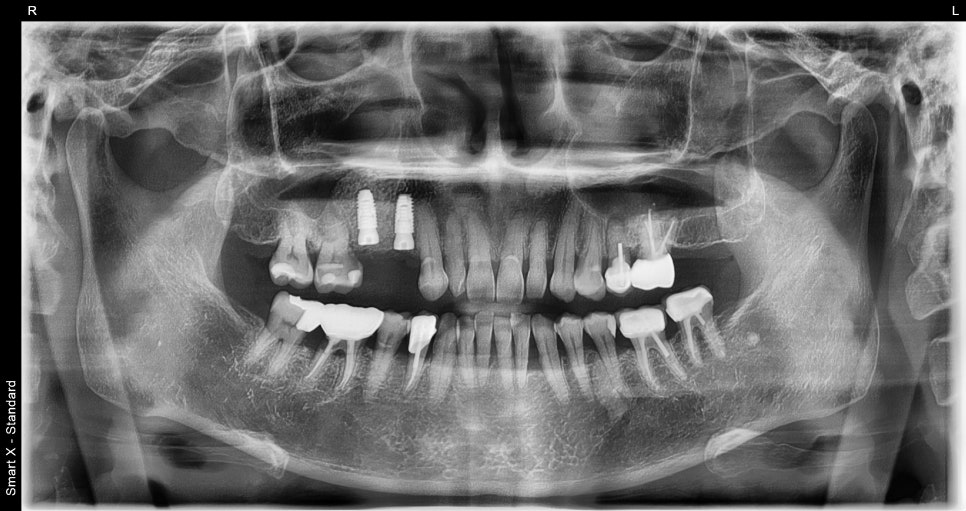

임플란트 전 검사

: 왜 CT·파노라마가 꼭 필요할까?

임플란트는 정확한 진단에서 시작됩니다.

서울오브치과병원에서는 파노라마 촬영과

CT 촬영을 통해 다음을 확인합니다.

잇몸뼈의 두께와 높이

신경의 위치

기존 염증 여부

주변 치아 상태

60대 환자분 역시 이 검사를 통해

“임플란트를 심기 전에 뼈를 보강해야 한다”는

결론을 얻었습니다.

Previous image Next image

이는 환자마다 뼈의 양 · 구조 · 잇몸 상태가

다르기 때문입니다.